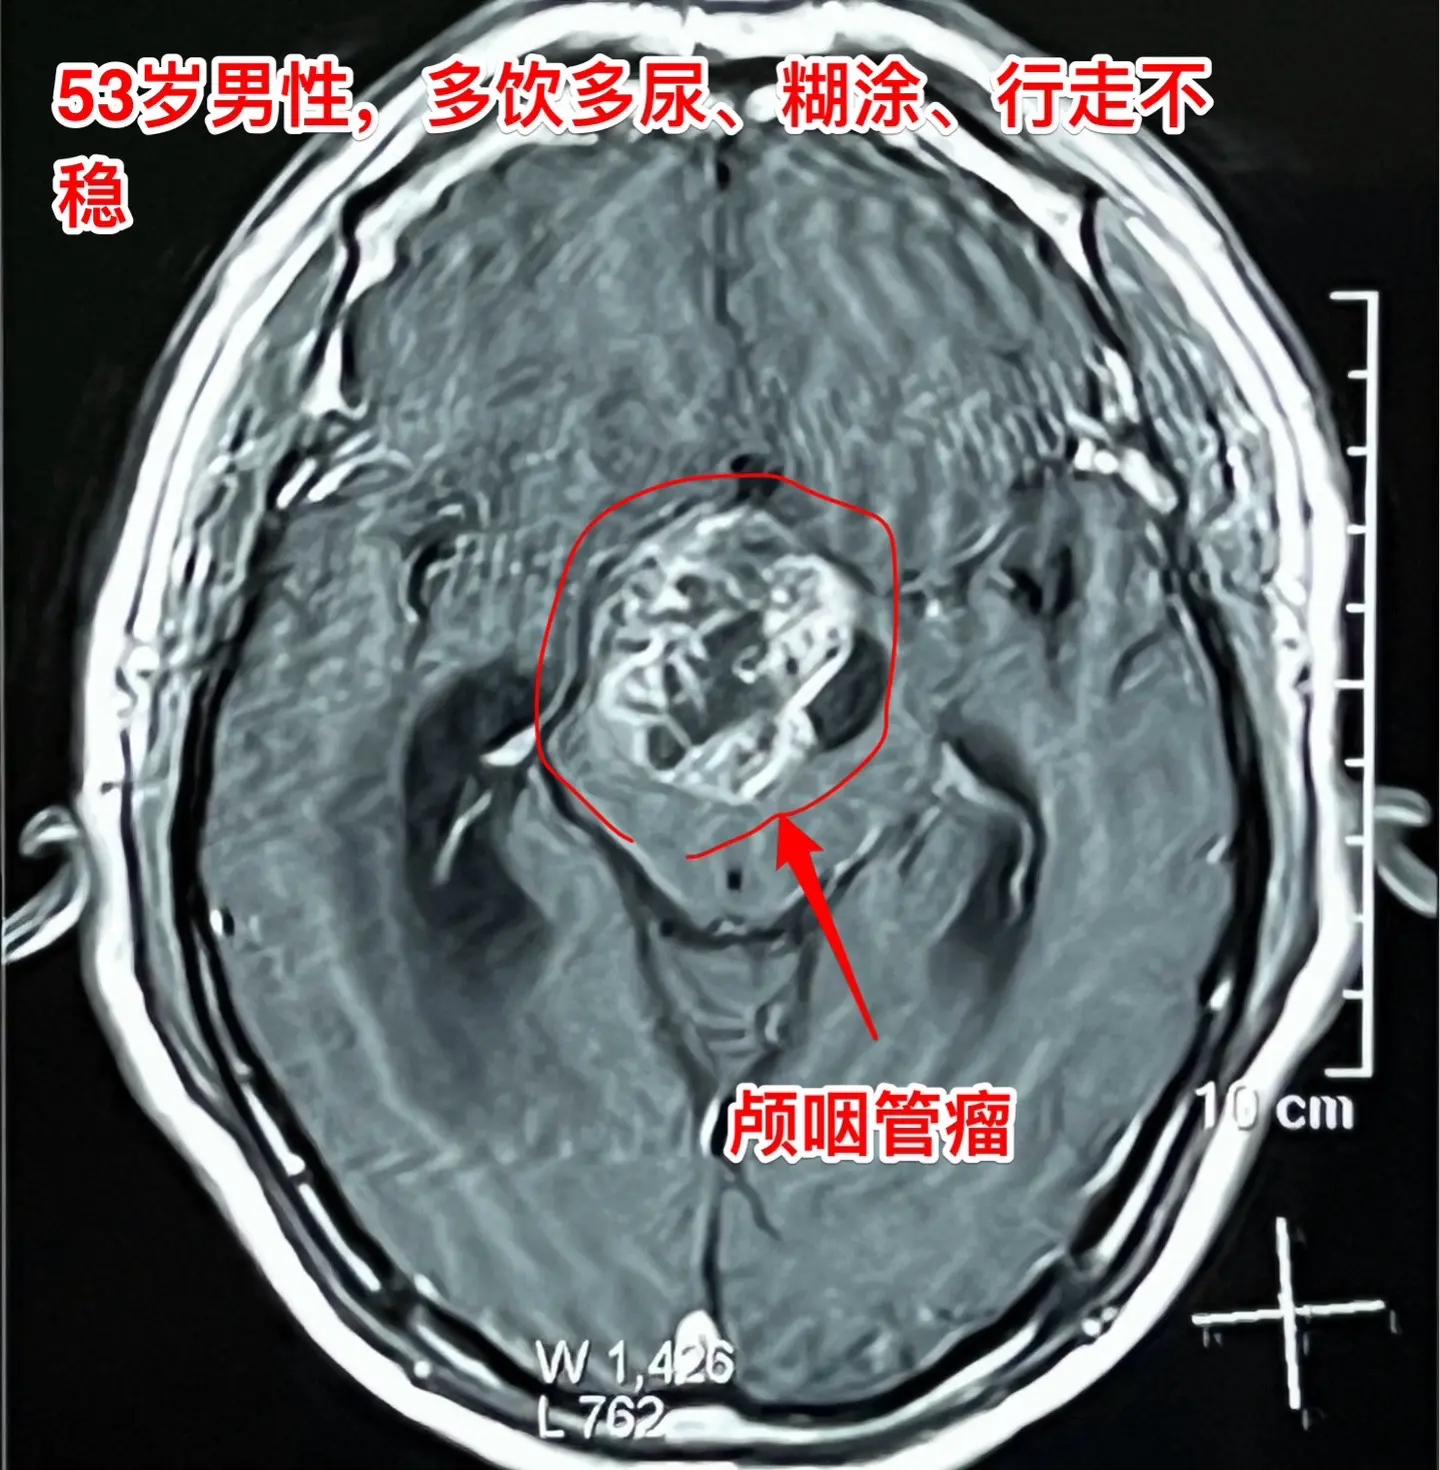

到医院作脑部磁共振检查,发现了脑部长了一个大肿瘤-颅咽管瘤,伴有脑积水。这个肿瘤直径接近5厘米,几乎是实性肿瘤,有很多的钙化斑,见图